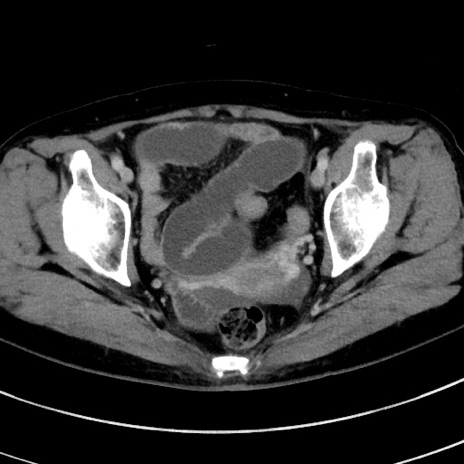

症例9(横断像)

【症例】 60歳代女性

【主訴】むかつき、みぞおちの痛み

【現病歴】3日前よりむかつきがあり、食事がとれない。

【既往歴】糖尿病

【身体所見】発熱なし、心窩部圧痛軽度あるも、腹膜刺激症状なし。

【データ】WBC 7400、CRP 1.92